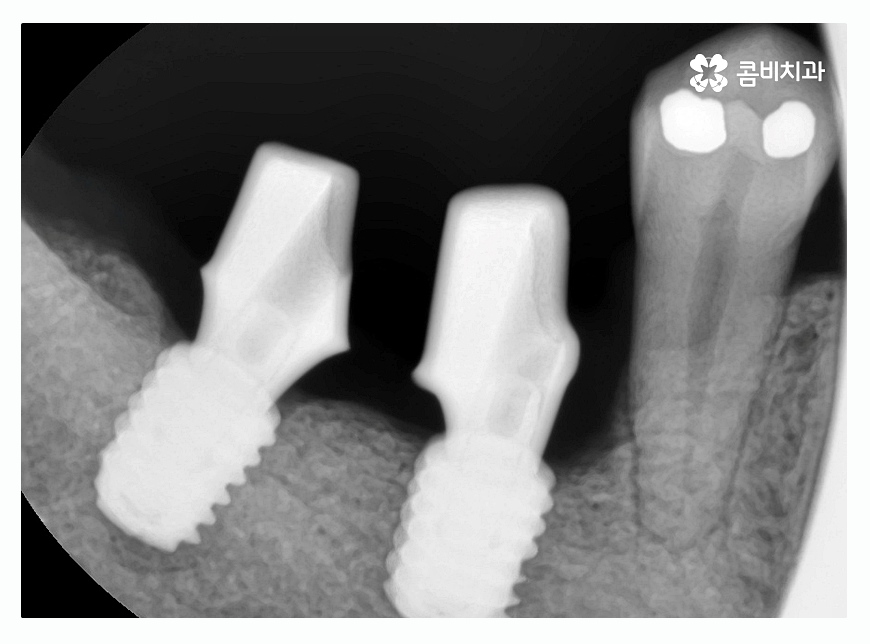

임플란트를 진행할 때 치조골에 치아의 뿌리 역할을 하는

인공 치근을 식립하고 잇몸 뼈와 골 유착이 튼튼하게

되도록 하는 과정을 거치게 되는데 뿌리 역할을 하는 만큼

잇몸의 상태가 건강해야 하고 뼈가 충분히 있어야

건강하게 치료를 진행할 수 있어요.

환자분들 개개인의 구강 상태와 치아의 상실 원인 등에

따라서 임플란트종류 및 치료 방법도 달라지게 되지만

임플란트는 자연치아의 심미성과 기능 등을 회복하는 치료이고

첫 치료가 중요하기 때문에 식립 각도와 사후 관리 등도

매우 중요한 부분이라고 할 수 있는데요.